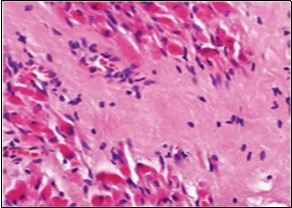

On microscopy, a collagen- rich, minimally cellular, fibrotic soft tissue nodule is exemplified which simulates a scar or conventional fibroma. The neoplasm is comprised of uniform, plump, fibroblastic or myo-fibroblastic cells encompassed in a collagen-rich stroma with infiltration and entrapment of skeletal myocytes 5, 6. Cogent histological examination depicts replacement of muscle fibres and muscle mass with fascicles of fibrous tissue comprised of mature fibroblastic cells, thereby conferring fibrosis 6. Figure 1, Figure 2, Figure 3, Figure 4, Figure 5, Figure 6, Figure 7, Figure 8.

Figure 2.Fibromatosis colli demonstrating fascicles of fibroblasts and myo-fibroblasts within an abundant collagenous stroma and several mature myocytes 10.